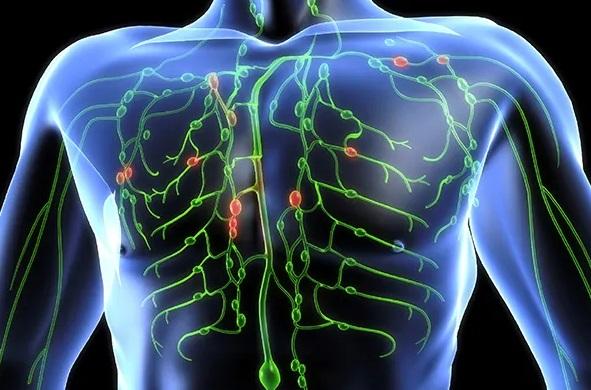

A X. agyidegünk a nervus vagus. Az ő aktivitása felel az ellazulásért, a kiegyensúlyozott testi dinamikákért, megfelelő belső szervi működésekért.

Testtartás – légzés – bolygóideg (n.vagus) Avagy a vagus terápia jelentőségéről másképp